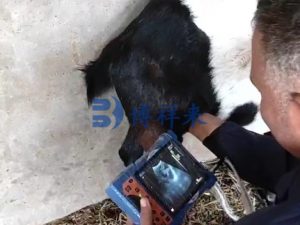

直肠检测还是腹壁检测?羊用B超机的两种方式

羊的妊娠检测主要有两种方式:直肠探头检测 和 腹壁检测。

2、腹壁检测的优势

在妊娠中后期,腹壁检测无需插入体内,更快、更方便,适合大规模排查。胎囊数量在30天以上仍可通过影像清晰区分。

许多羊场会根据生产要求选择不同的检测方式,但无论是哪种方法,高分辨率的 羊用B超机 都能让检查结果更加直观。